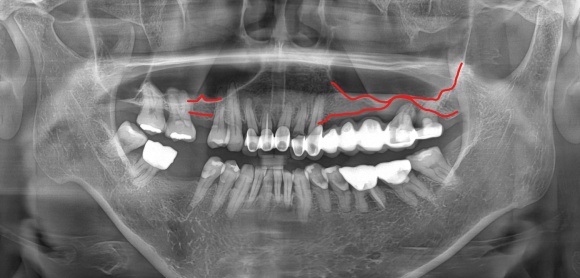

③ 상악동 거상술이 동반되는 위 어금니

위턱 뼈에는 '상악동'이라는 공기주머니가 있어 뼈의 두께가 얇은 경우가 많습니다.

임플란트를 안전하게 식립할 깊이가 확보되지 않을 때 상악동 막을 들어 올리고 공간을 확보하는 과정이 필요합니다.

정직한 의료진은 3D CT 데이터 등 객관적인 자료를 바탕으로 환자가 충분히 이해할 수 있도록 설명해 줄 것입니다.